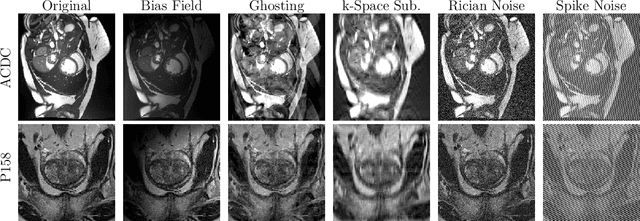

Abstract:Medical image segmentation models are often trained on curated datasets, leading to performance degradation when deployed in real-world clinical settings due to mismatches between training and test distributions. While data augmentation techniques are widely used to address these challenges, traditional visually consistent augmentation strategies lack the robustness needed for diverse real-world scenarios. In this work, we systematically evaluate alternative augmentation strategies, focusing on MixUp and Auxiliary Fourier Augmentation. These methods mitigate the effects of multiple variations without explicitly targeting specific sources of distribution shifts. We demonstrate how these techniques significantly improve out-of-distribution generalization and robustness to imaging variations across a wide range of transformations in cardiac cine MRI and prostate MRI segmentation. We quantitatively find that these augmentation methods enhance learned feature representations by promoting separability and compactness. Additionally, we highlight how their integration into nnU-Net training pipelines provides an easy-to-implement, effective solution for enhancing the reliability of medical segmentation models in real-world applications.